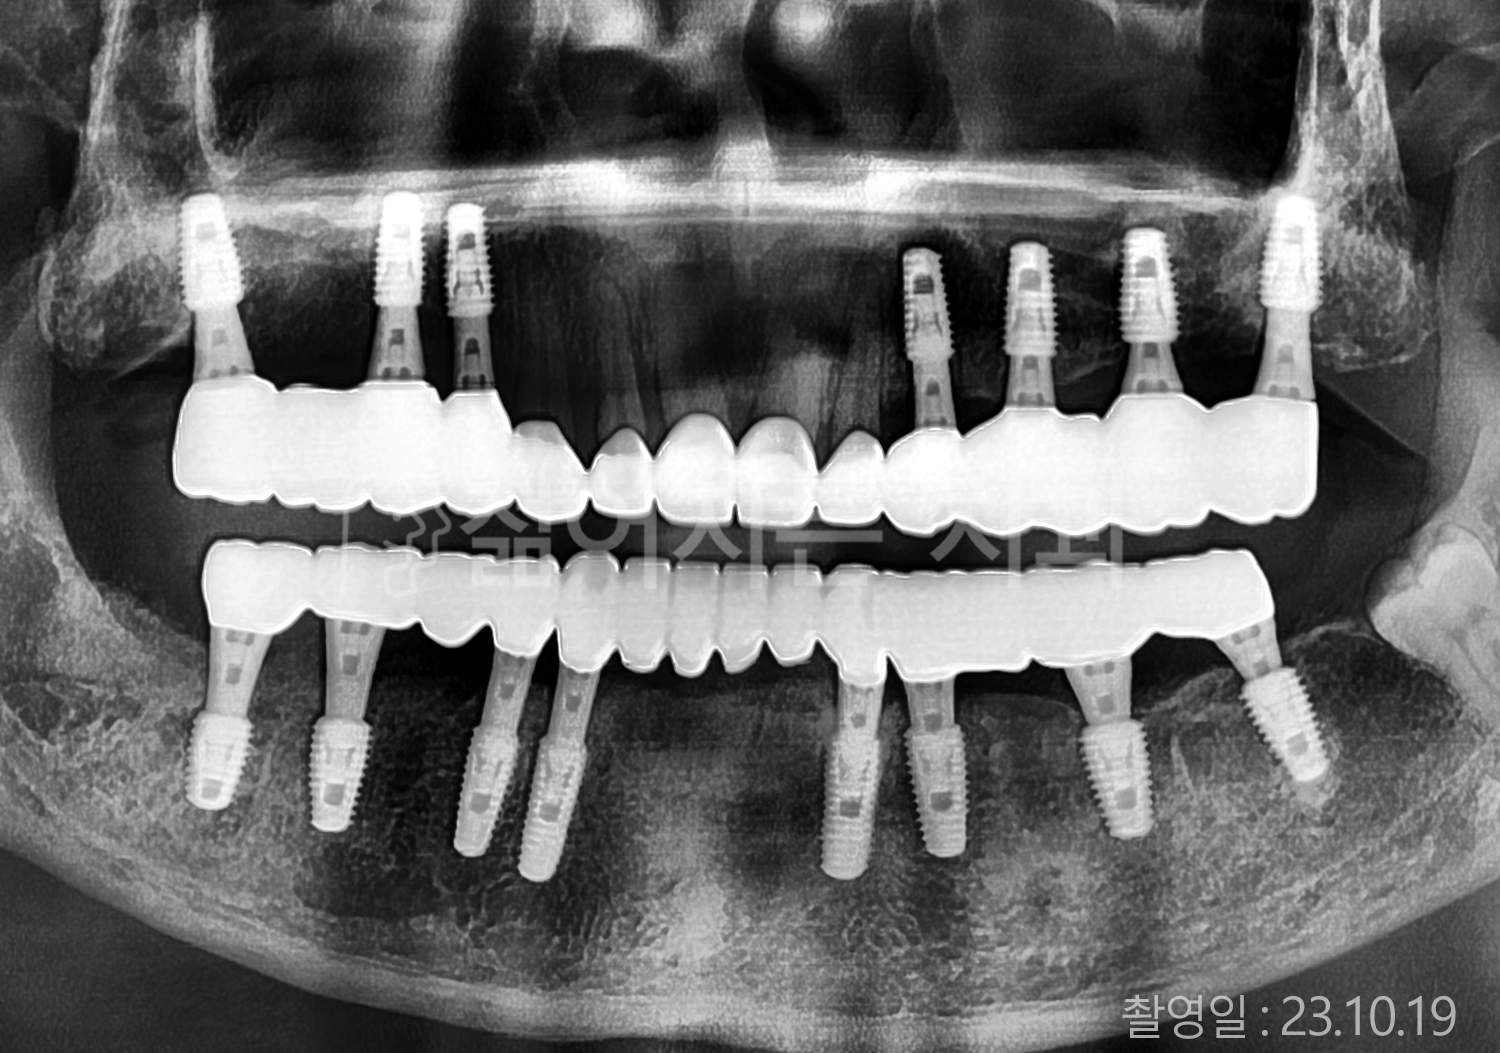

• 80대 전체치아 10개 이상 임플란트

• 60대 고혈압, 당뇨, 고지혈증 전체치아 10개 이상 임플란트

• 60대 전체치아 10개 이상 임플란트

• 60대 고혈압, 고지혈증 전체치아 10개 이상 임플란트

• 50대 고혈압, 당뇨, 고지혈증 전체치아 10개 이상 임플란트

• 70대 골다골증, 파킨스병 전체치아 10개 이상 임플란트

• 40대 전체치아 10개 이상 임플란트

• 60대 골다골증 전체치아 10개 이상 임플란트

• 40대 고혈압 전체치아 10개 이상 임플란트

• 50대 전체치아 10개 이상 임플란트

• 70대 전체치아 10개 이상 임플란트